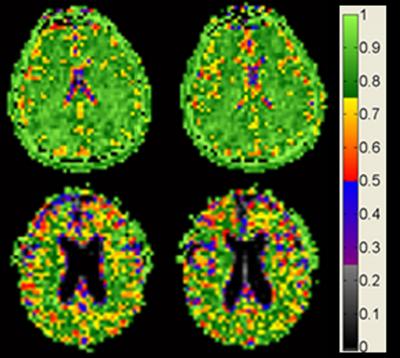

Cell density remains constant as brain shrinks with age

Brain cell density remains constant with age among cognitively normal adults. Image credit goes to: Dr. Keith Thulborn

New, ultra-high-field magnetic resonance images (MRI) of the brain by researchers at the University of Illinois at Chicago provide the most detailed images to date to show that while the brain shrinks with age, brain cell density remains constant. The images provide the first evidence that in normal aging, cell density is preserved throughout the brain, not just in specific regions, as previous studies on human brain tissue have shown.